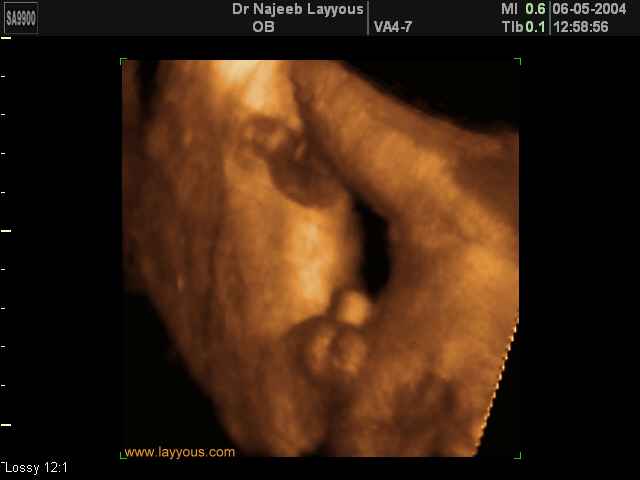

- Fetal Parts Ultrasound Scan Photos